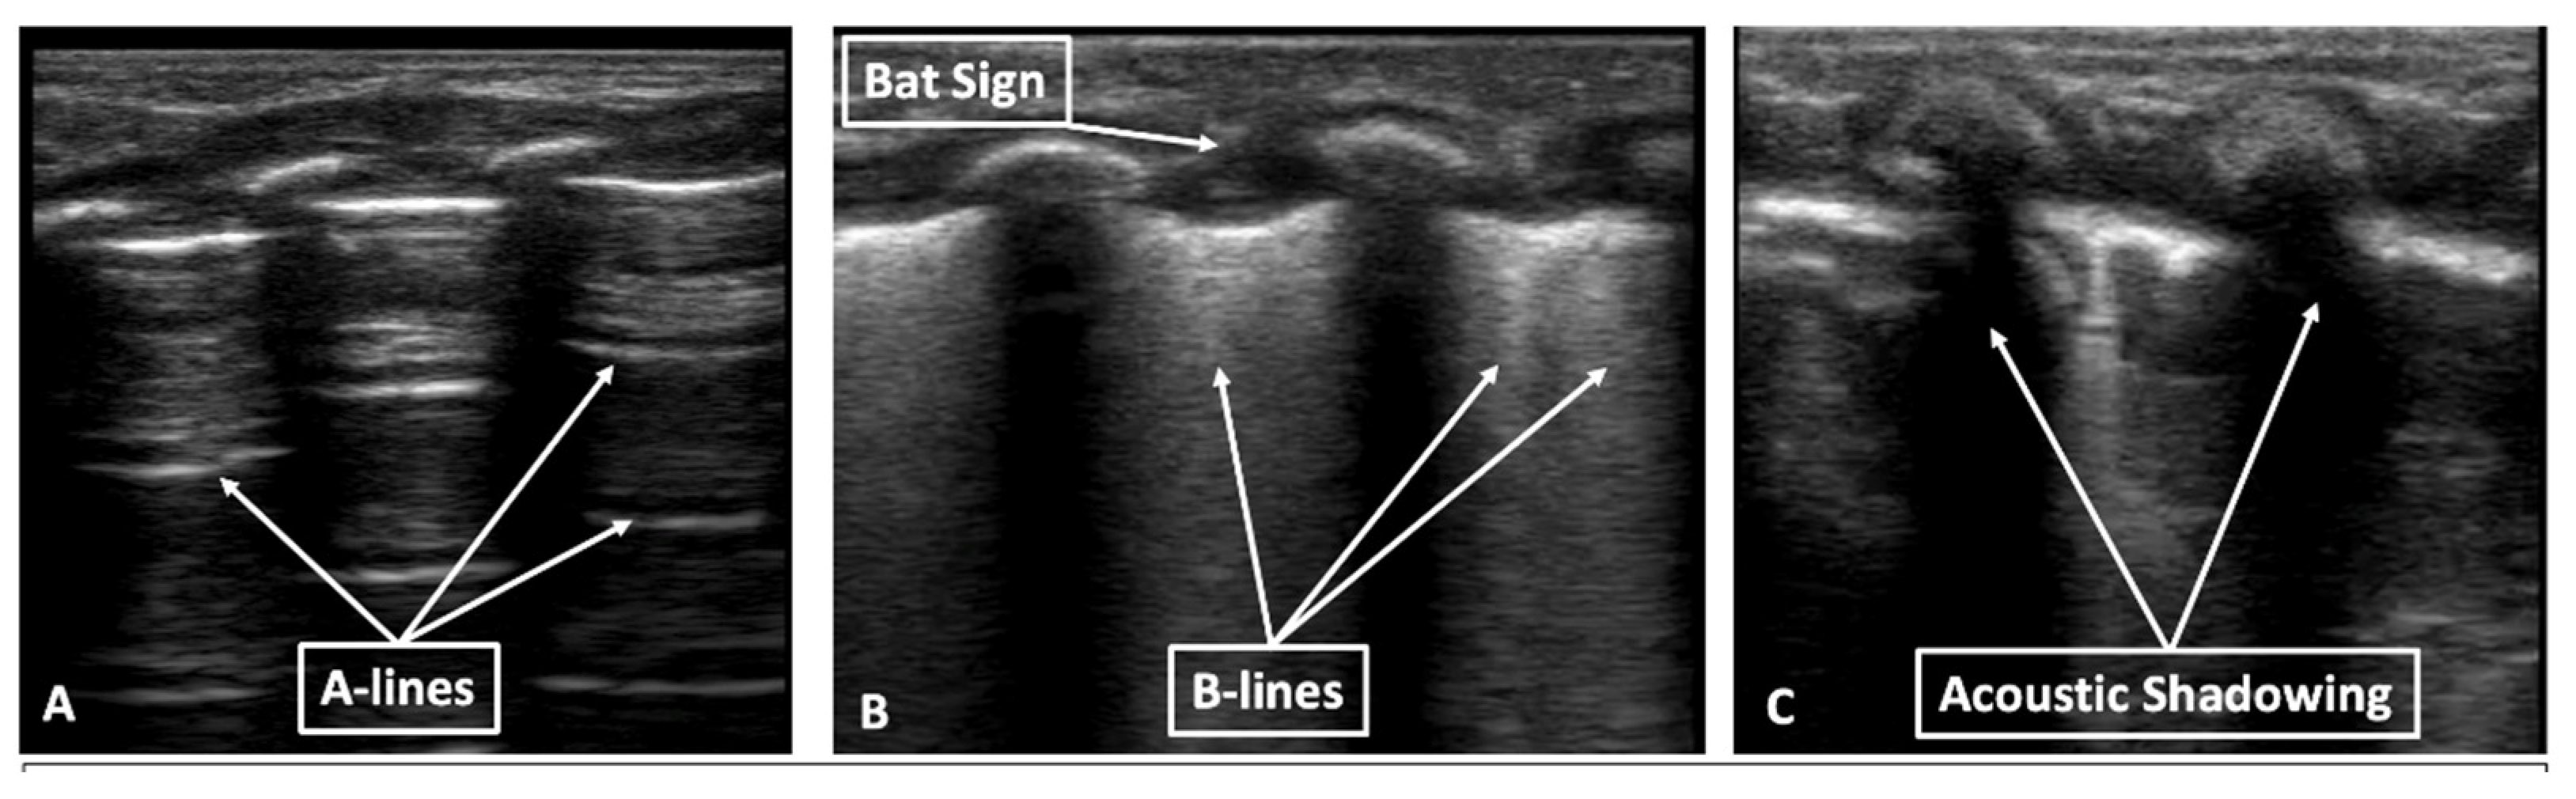

1.2. Lung Ultrasound Terminology

1.2.2. A-Lines

1.2.3. B-Lines